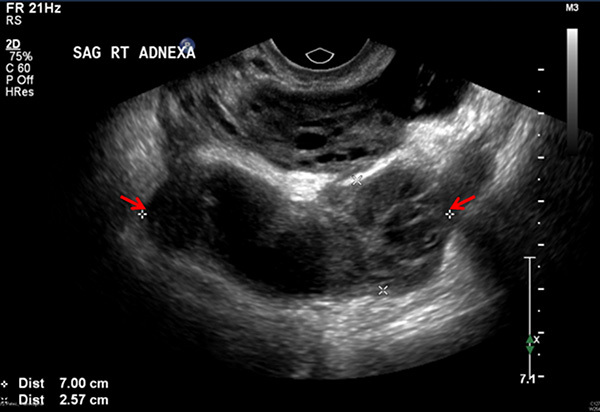

When TOA is suspected, imaging to rule out the condition should be performed promptly. On both ultrasound and contrast-enhanced CT imaging, TOA manifests as a complex fluid collection with internal septations. (See Figures 1 and 2.) Surrounding nonspecific inflammatory changes likely will be seen, such as fat stranding on CT scan and free fluid in the cul-de-sac. Air within the structure is less common but may be present. The differential diagnosis for these findings includes a complex ovarian neoplasm, and the clinician should use systemic findings to help differentiate the two.26

Figure 1. Transvaginal Ultrasound Showing a Sagittal View of the Right Adnexa with a Fluid Collection (between the arrows) |

Image courtesy of Basil Hubbi, MD, Department of Radiology, Rutgers New Jersey Medical School. |